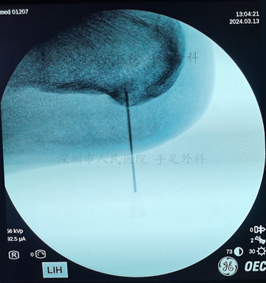

图10:采用关节镜微创技术清理病变组织和增生骨刺,术中定位病变部位

图11:术中X光示骨刺已清除